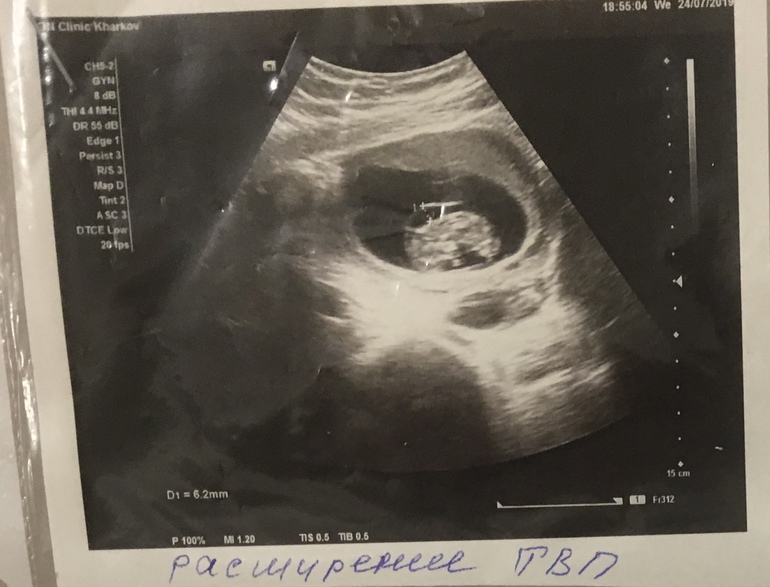

Толщина воротникового пространства ТВП- 6,2!!

Все остальные показатели в норме, меня смутило, что КТР 38 мм, но в литературе я прочла что твп измеряется при 45-84 мм

ваш КТР на 10+5 недель, это рано для скрининга.